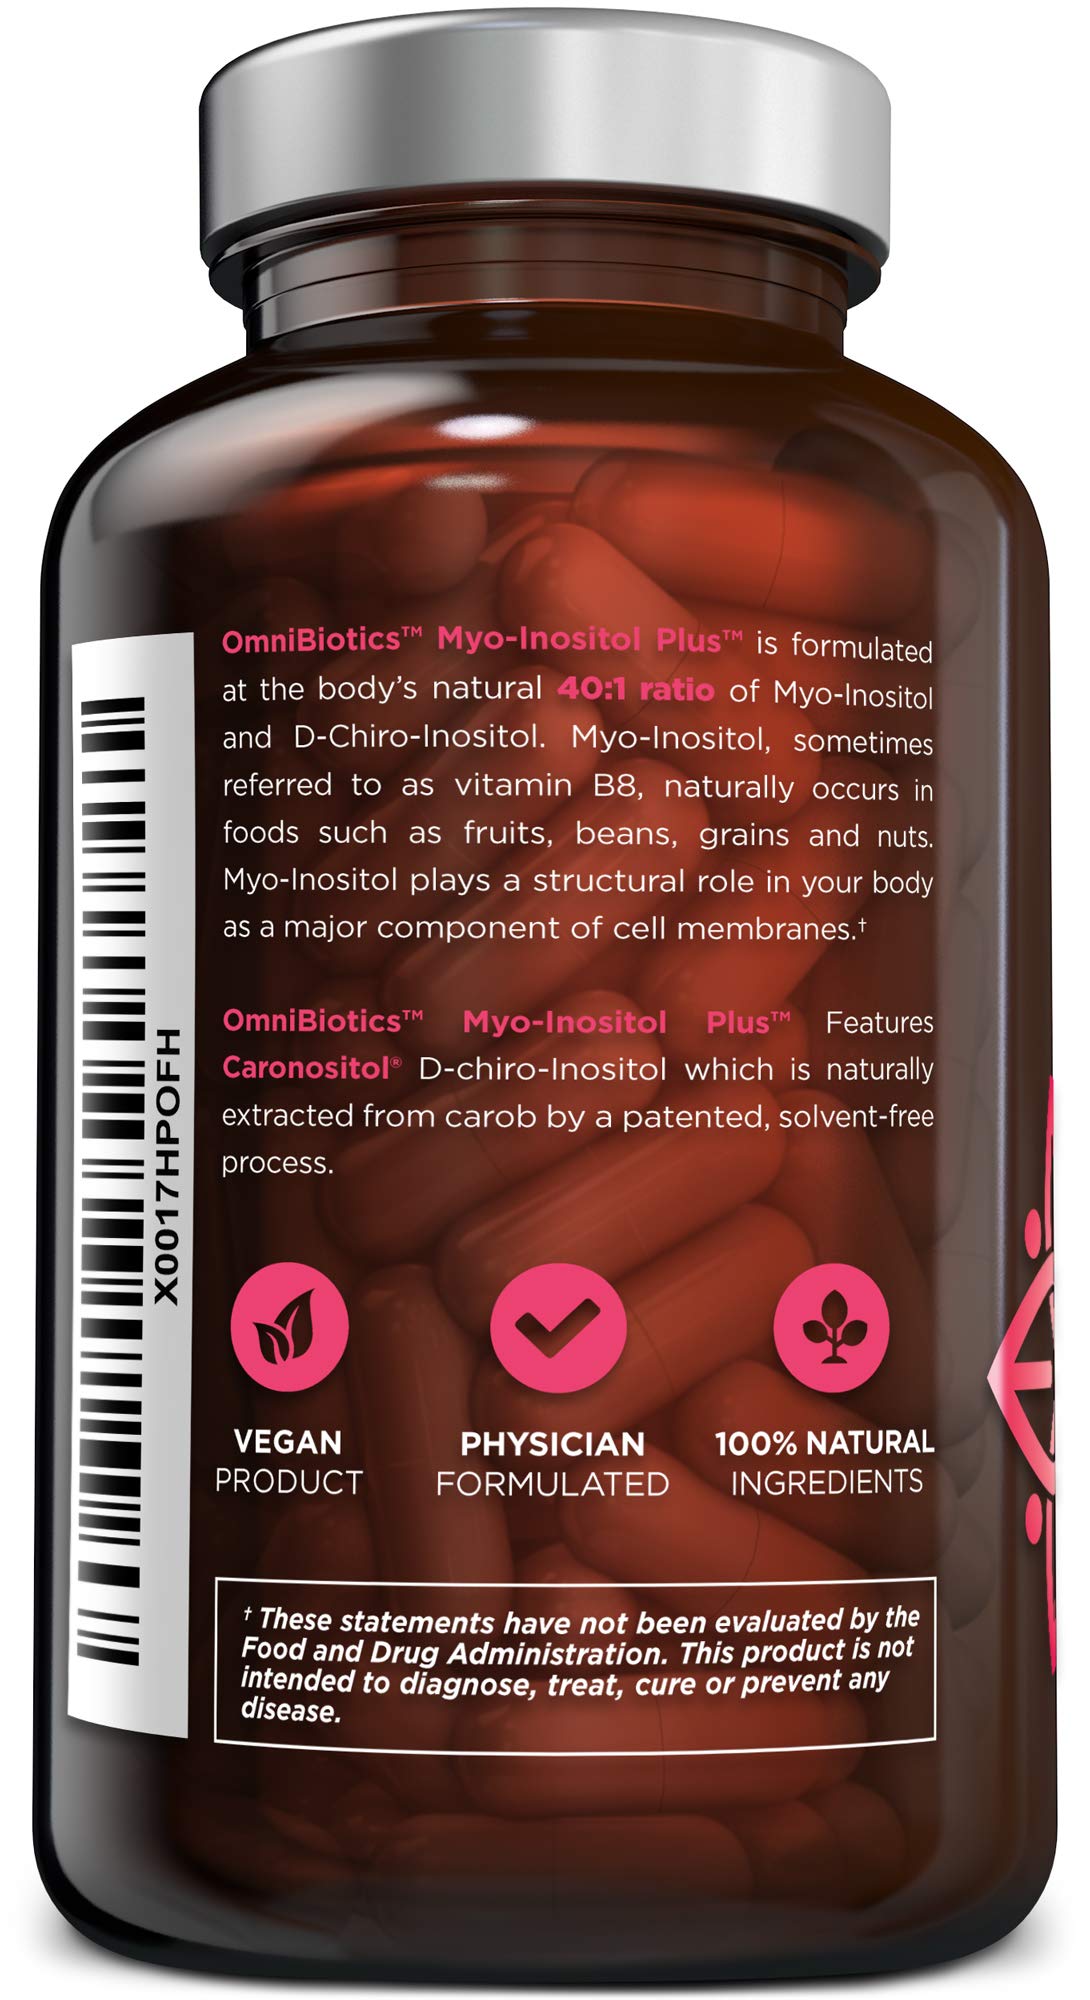

Myo-Inositol Plus & D-Chiro-Inositol | PCOS Supplement | Helps Promote Hormone Balance and Support Ovarian Function | Natural Fertility Supplements (120 Capsules)

Description

Myo-Inositol is the most abundant form of inositol which is an important

nutrient to help support the female reproductive system. D-Chiro-Inositol has

been studied for its ability to improve absorption and bioavailability.

OmniBiotics Myo-Inositol Plus with Caronositol features myo-inositol and

d-chiro-inositol at 2,000 mg and 50 mg each respectively, per serving. Myo-

Inositol Plus is a safe and effective myo inositol with d chiro supplement

option. 120 veggie caps 30 day supply These statements have not been

evaluated by the FDA. This product is not intended to diagnose, treat, cure,

or prevent any disease. Caronositol is natural D-chiro-inositol botanical

extract (minimum 95%) purified from carob pod by a solvent-free patented

process. ‣ Made In the USA within a FDA inspected, NSF and cGMP certified

facility ‣ 100% vegetarian / vegan friendly, Non-GMO ‣ Contains no gluten,

wheat, dairy soy, yeast, animal products, artificial colors, or artificial

preservatives

Features:

- HORMONE + FERTILITY + MENSTRUAL CYCLE SUPPORT Specially formulated for women, Myo-inositol Plus contains ingredients that are clinically proven to naturally help support hormone balance, help maintain ovarian function, promote healthy menstrual cycles, and support egg quality. Myo-Inositol Plus is a 100% natural fertility supplement, designed to promote overall reproductive health.

- MOST EFFECTIVE 40:1 RATIO Studies show that the bodys natural 40:1 ratio of Myo-Inositol to D-Chiro-Inositol is the most effective ratio for fertility and reproductive support. Myo-Inositol Plus offers this clinically-proven 40:1 ratio and features Caronositol, a natural D-chiro-inositol (DCI) botanical extract (minimum 95%), purified from carob pods through a solvent-free patented process.

- PROMOTES EMOTIONAL WELLNESS + MOOD Myo-Inositol is widely used to help support energy and promote an overall feeling of well-being because the brains natural neurotransmitters (dopamine, norepinephrine, serotonin, acetylcholine, and GABA) rely on inositol to relay messages. Myo-Inositol Plus was designed to maximize these positive emotional effects.

- SUPPORTS WELL-BEING Myo-Inositol is included in our formula for its contribution to overall women's health, with a focus on promoting balance and well-being in the body. It is designed to complement a healthy lifestyle, supporting the body's natural processes.

- 100% NATURAL, NON-GMO, NO BINDERS or ADDITIVES Our clinical-strength, Myo-Inositol Plus supplement is 100% free of: gluten, soy, nuts, dairy, sugar, animal by-products, artificial ingredients, chemicals, preservatives and fillers. We also do testing at every stage of the manufacturing process to ensure all ingredients are free of heavy metals. Made in the USA in a NSF-certified, FDA-registered, cGMP facility.